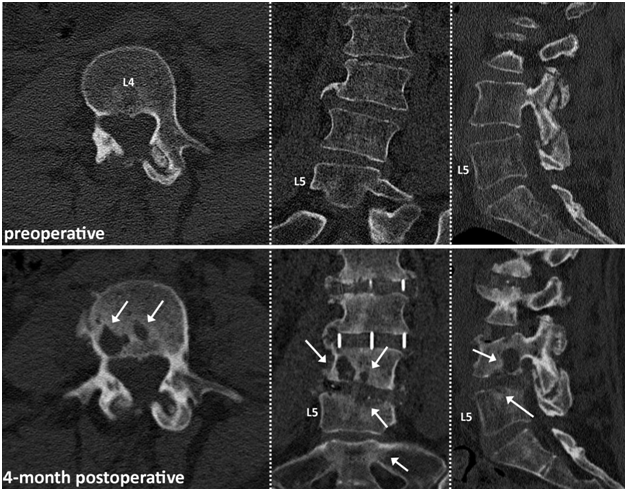

At the time of the reporting, stability was preserved in the remaing two patients and they did not require further surgical treatment to address the osteolytic destructions (Figures 2&3). Total follow-up times for patients were 29, 22, and 6 months, for patient 1, 2, 3 respectively.

Figure 3 67-year old female patient with 3 level LLIF procedure at L2-L5. White arrows indicating osteolytic bone destruction starting at the vertebral endplates on the weight bearing surfaces of the LLIF cage of the L4-L5 level 4 month postoperatively.